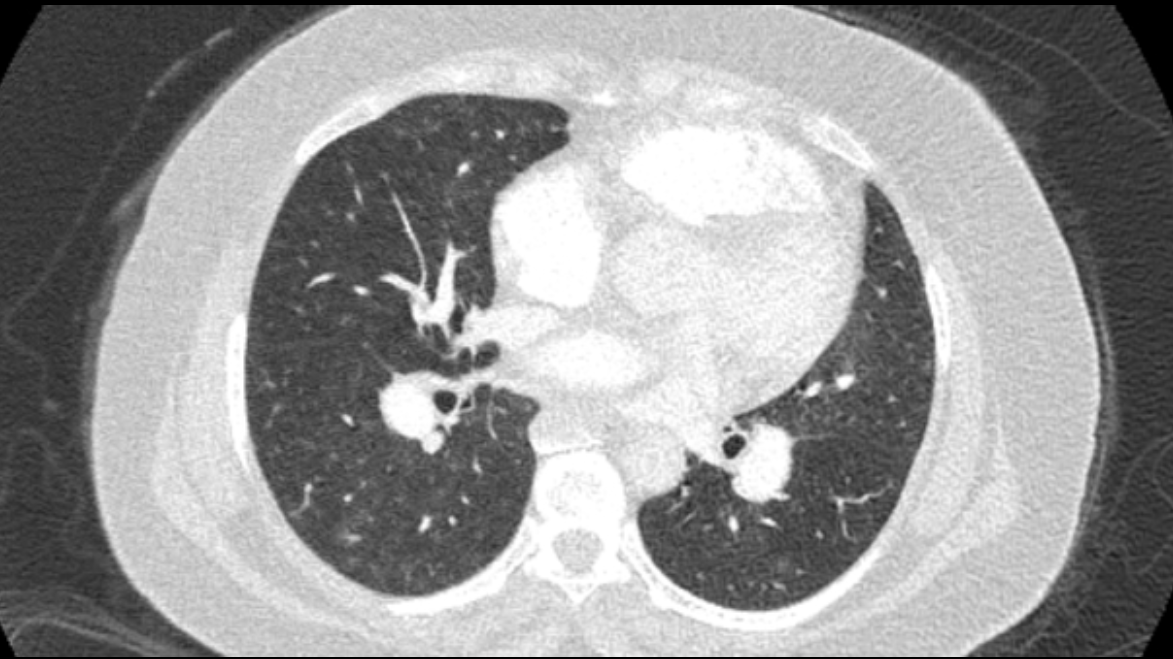

Title: Accessory right inferior hepatic vein [Uncaptioned image] [Uncaptioned image]

Discussion:Marked dilatation of the pulmonary trunk (6.7 cm) with the right (5.4 cm) and left (4 cm) main branches. Lung window shows mild bilateral diffuse faint groundglass centrilobular lung nodules that may reflect an underlying infection. Scans through the upper abdomen revealed average size cirrhotic liver and reflux of contrast into the IVC and hepatic veins with Incidental opacification of accessory right inferior hepatic vein…